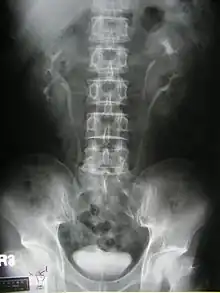

Duplicated ureter

Duplicated ureter or duplex collecting system is a congenital condition in which the ureteric bud, the embryological origin of the ureter, splits (or arises twice), resulting in two ureters draining a single kidney. It is the most common renal abnormality, occurring in approximately 1% of the population.[1][2]

Diagnosis

Prenatally diagnosed hydronephrosis (fluid-filled kidneys) suggest post-natal follow-up examination. The strongest neo-natal presentation is urinary tract infection. A hydronephrotic kidney may present as a palpable abdominal mass in the newborn, and may suggest an ectopic ureter or ureterocele. In older children, ureteral duplication may present as: